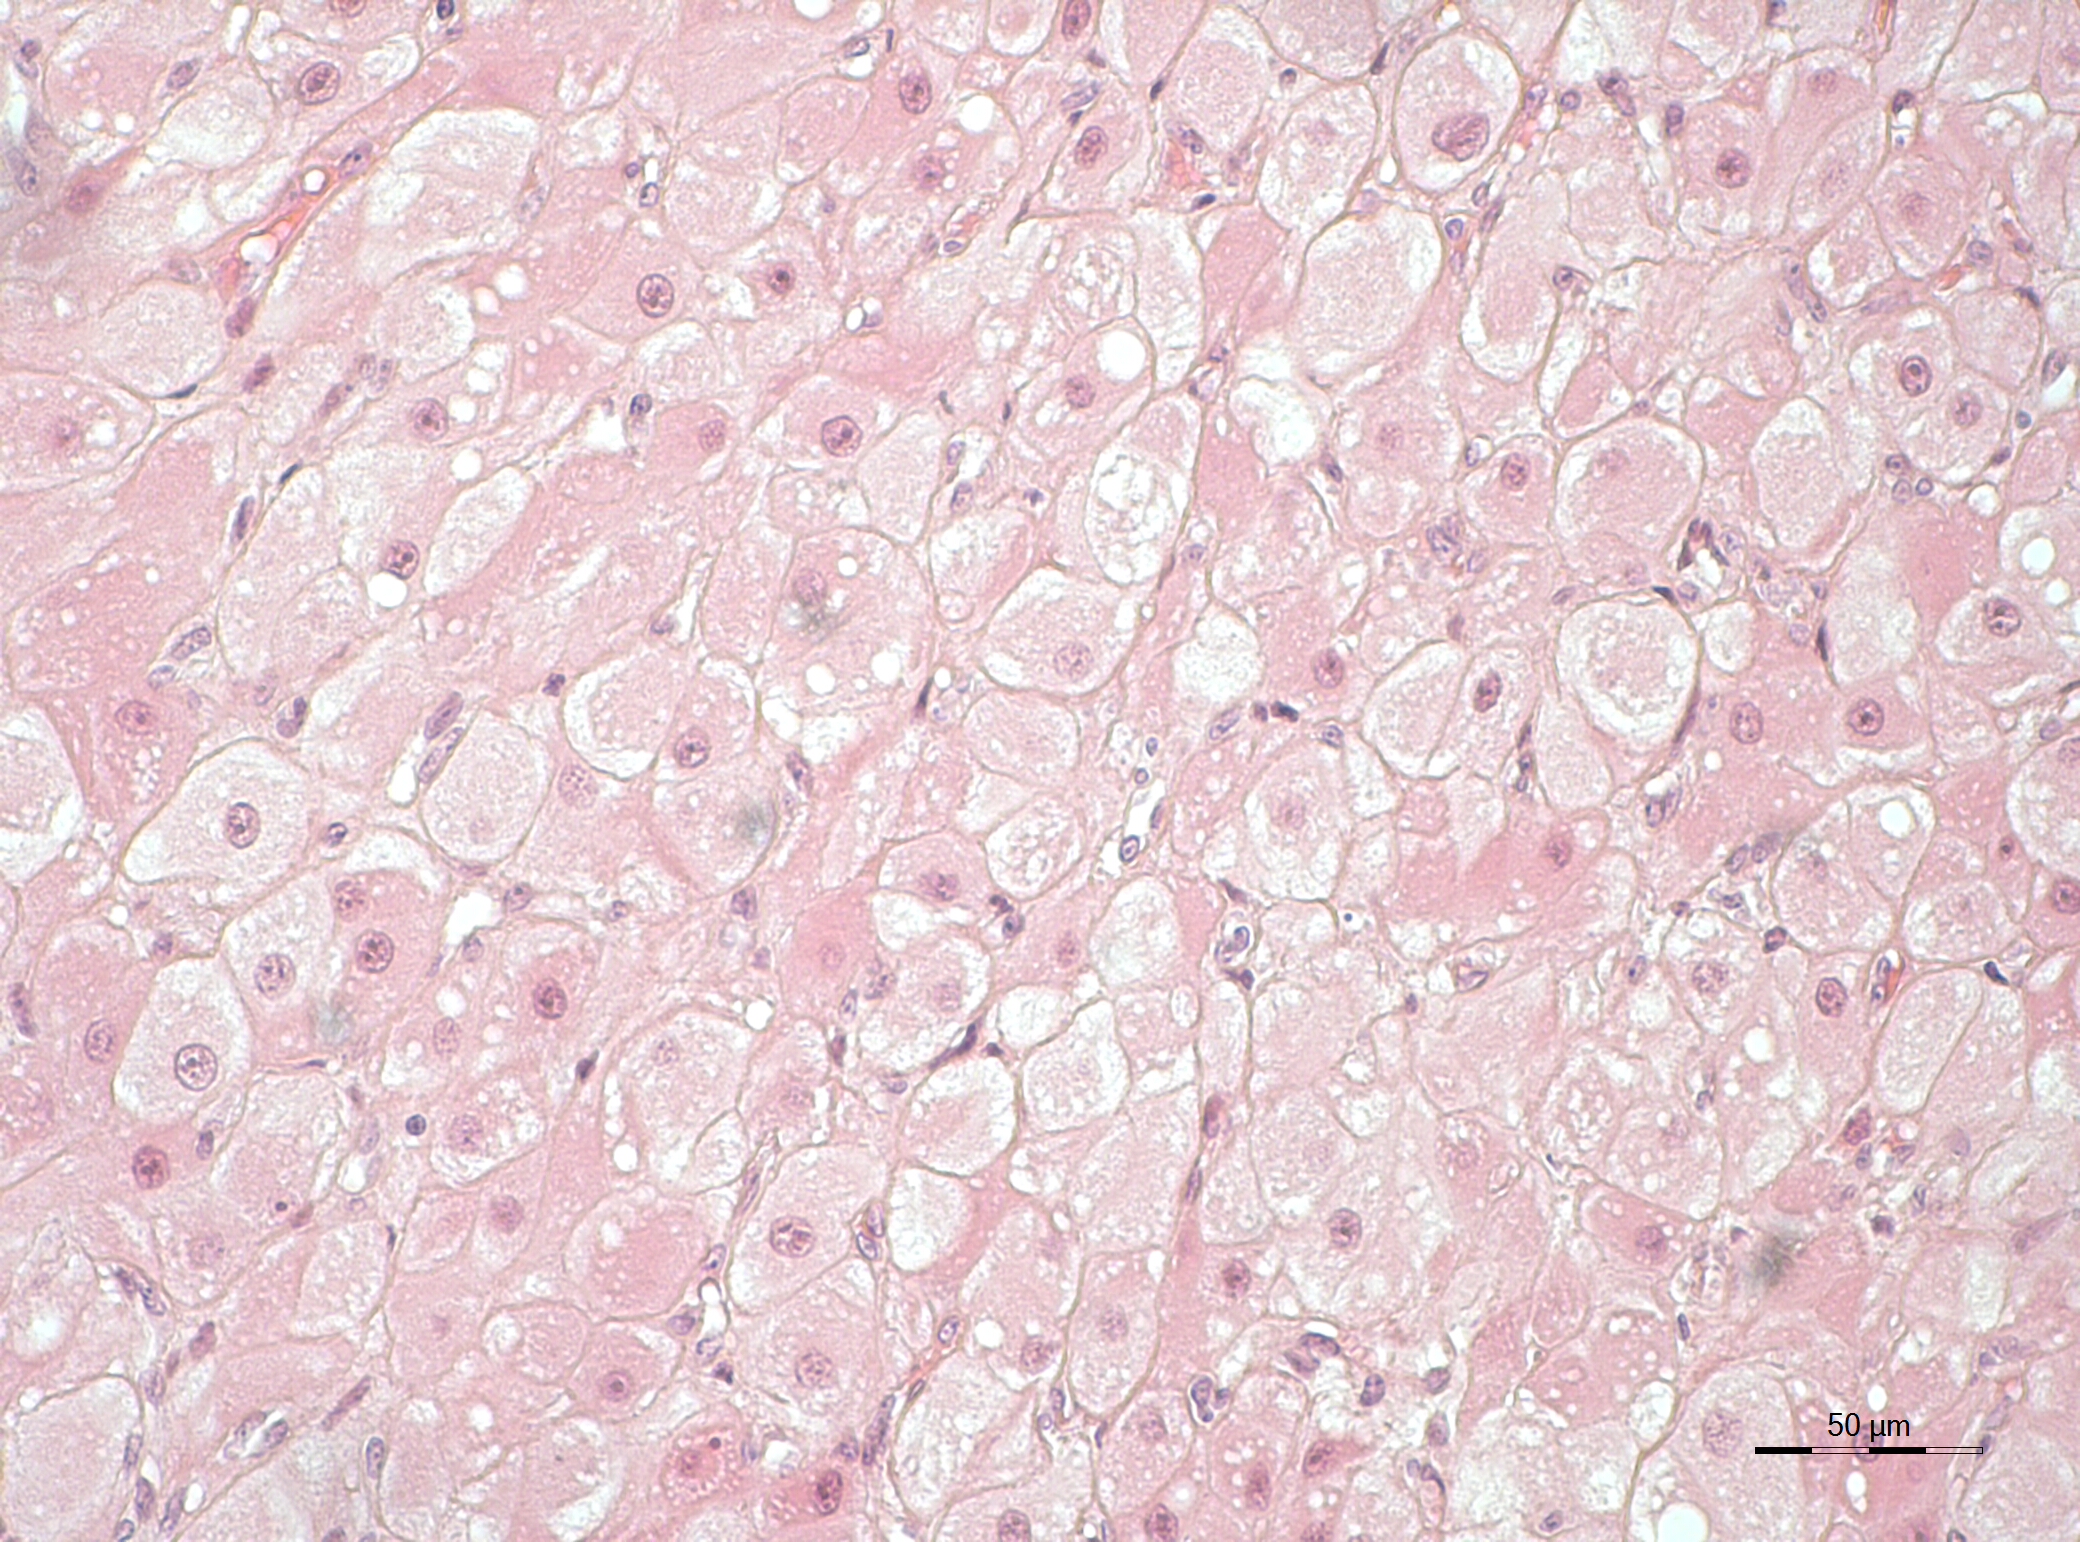

"We succeeded in isolating and culturing cells from the corpus luteum of domestic cats which were functionally active in the sense that they produced progesterone. This allowed us to measure the regulatory effects of different hormones on these cells," says Beate Braun, Leibniz-IZW head of the study. The cell culture methodology allows studies to be conducted without having to directly perform experiments on the animals themselves, be they domestic or wild. In the studies, the effect of a potentially corpus luteum-preserving hormone (LH - luteinizing hormone) and a potentially corpus luteum-degrading hormone (PGF2α - prostaglandin F2α) were tested. The team showed that the cultured cells responded to the chosen hormones and produced more or less progesterone, depending on the hormone used and the developmental stage of the corpus luteum from which they were isolated.

“We first established our technique in the domestic cat. We then succeeded to adjust the method and apply it to our rare sample material from wild cat species, including African and Asiatic lions, Asiatic golden cat and Java leopard. This shows that it is possible to use related animal species to obtain the necessary knowledge and then translate the newly developed techniques to endangered species,” explains Michał Hryciuk, who will use these successful studies to complete his doctoral thesis in reproductive biology. The next goal of the scientists will be to also target lynx corpus luteum cells to study the mechanisms which ensure luteal longevity.